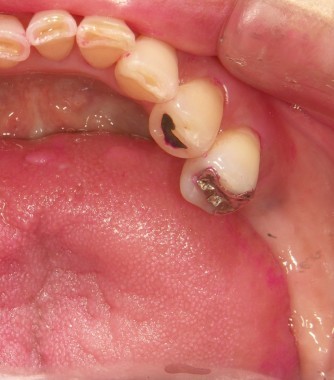

インプラントの術前・術後 Kさん